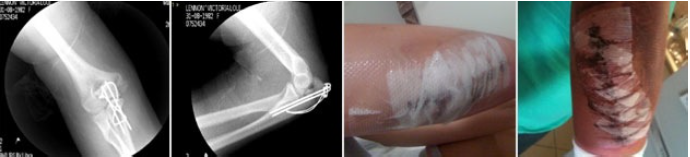

After badly breaking my elbow in a biking accident, I underwent a full reconstruction surgery along with wire and pins fitted to my elbow joint. I sought assistance from Matt approximately 6 months post surgery to relieve pain in my elbow and associated pain in my neck, back and shoulder. In addition to this, I had limited mobility and nerve injury in the joint. Matt was able to identify and treat these areas extremely effectively due to his in depth knowledge of the human body and muscular-skeletal therapies.

Following my first reconstruction, Matt treated me on a monthly basis to assist with movement, mobility and pain management through manipulation and myofascial release of muscles. I required a second reconstruction to remove pins and wires and further reconstruct the joint after sustaining such serious injury initially. Matt assisted in release and preparation both physically and mentally before surgery and post surgery care. After the initial injury, my confidence had suffered also. Post surgery, Matt assisted with movement, massage and muscle release. I had extensive bruising and pain from the surgery and Matt’s techniques and treatment significantly improved my recovery timeframe and healing, particularly in comparison to my first reconstruction. Matt has been a key ingredient in my successful recovery both physically and emotionally. I have found him to be a knowledgable and dedicated professional and would not have such good results should I have been without his expertise and care.